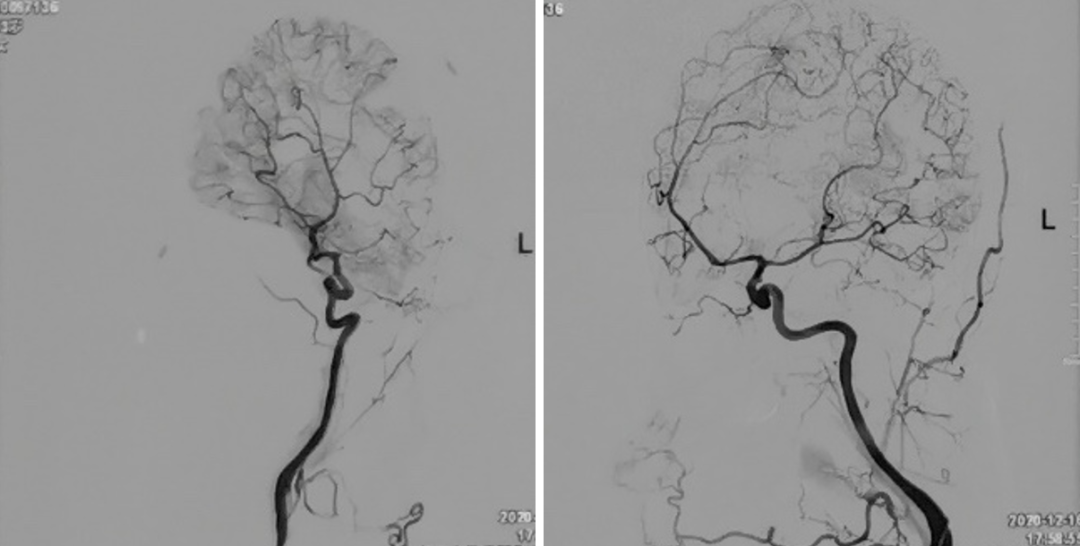

今天为大家分享的是,由复旦大学附属华山医院顾宇翔教授和倪伟医师带来的:巨大复杂颈内动脉分叉部动脉瘤一例,欢迎阅读、分享。

术前诊断: